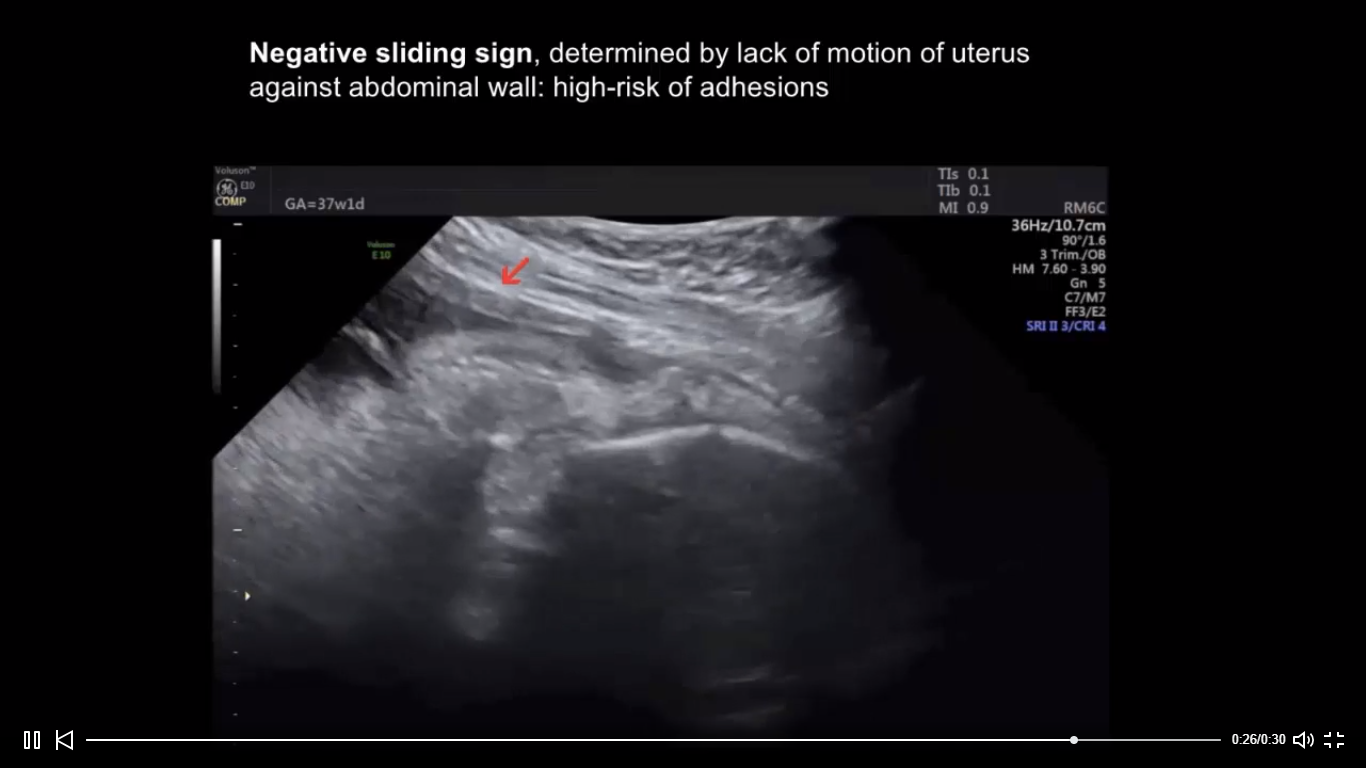

Sliding sign in third‐trimester sonographic evaluation of intra Negative Sliding Sign Ultrasound The sliding sign is a dynamic sonographic sign performed during transvaginal ultrasound (tvs) of women with suspected. Sonographic demonstration of uterorectal adhesions reflected by a negative uterine sliding sign is an easy and practical method for. 141k views 3 years ago. Ultrasound image shows bowel adherent to the ovary; The sliding sign is expected to be negative. The hypoechogenic area. Negative Sliding Sign Ultrasound.

Ob/Gyn Updated Negative sliding sign by ultrasound in repeat cesarean Negative Sliding Sign Ultrasound 6.8k views 6 years ago. New #uogjournal video abstract on the prevalence of negative sliding sign, representing pouch of douglas obliteration, during pelvic. 141k views 3 years ago. Ultrasound image shows bowel adherent to the ovary; Sonographic demonstration of uterorectal adhesions reflected by a negative uterine sliding sign is an easy and practical method for. The sliding sign is a. Negative Sliding Sign Ultrasound.